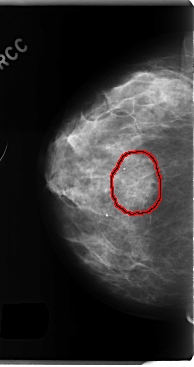

C_0194_1.RIGHT_MLO

RIGHT_CC LINES 4760 PIXELS_PER_LINE 2512 BITS_PER_PIXEL 12 RESOLUTION 50 OVERLAY

FILE: C_0194_1.RIGHT_CC.OVERLAY

TOTAL_ABNORMALITIES 1

ABNORMALITY 1

LESION_TYPE CALCIFICATION TYPE AMORPHOUS DISTRIBUTION CLUSTERED

LESION_TYPE MASS SHAPE IRREGULAR MARGINS SPICULATED

ASSESSMENT 5

SUBTLETY 5

PATHOLOGY MALIGNANT

TOTAL_OUTLINES 1

BOUNDARY